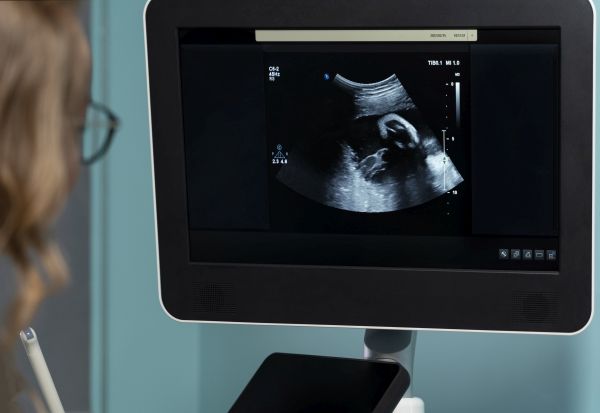

Со помош на ултразвук, хирурзите од Бостонската детска болница и Женската болница во САД користеле емболизација за лекување ретка пренатална состојба - деформитет на Галеновата вена.

Затоа Орбах и неговите колеги спровеле клиничко испитување, за да ја проценат можноста за лекување на оваа состојба, пред раѓањето. Нивниот пациент бил фетус во 34. гестациска недела.